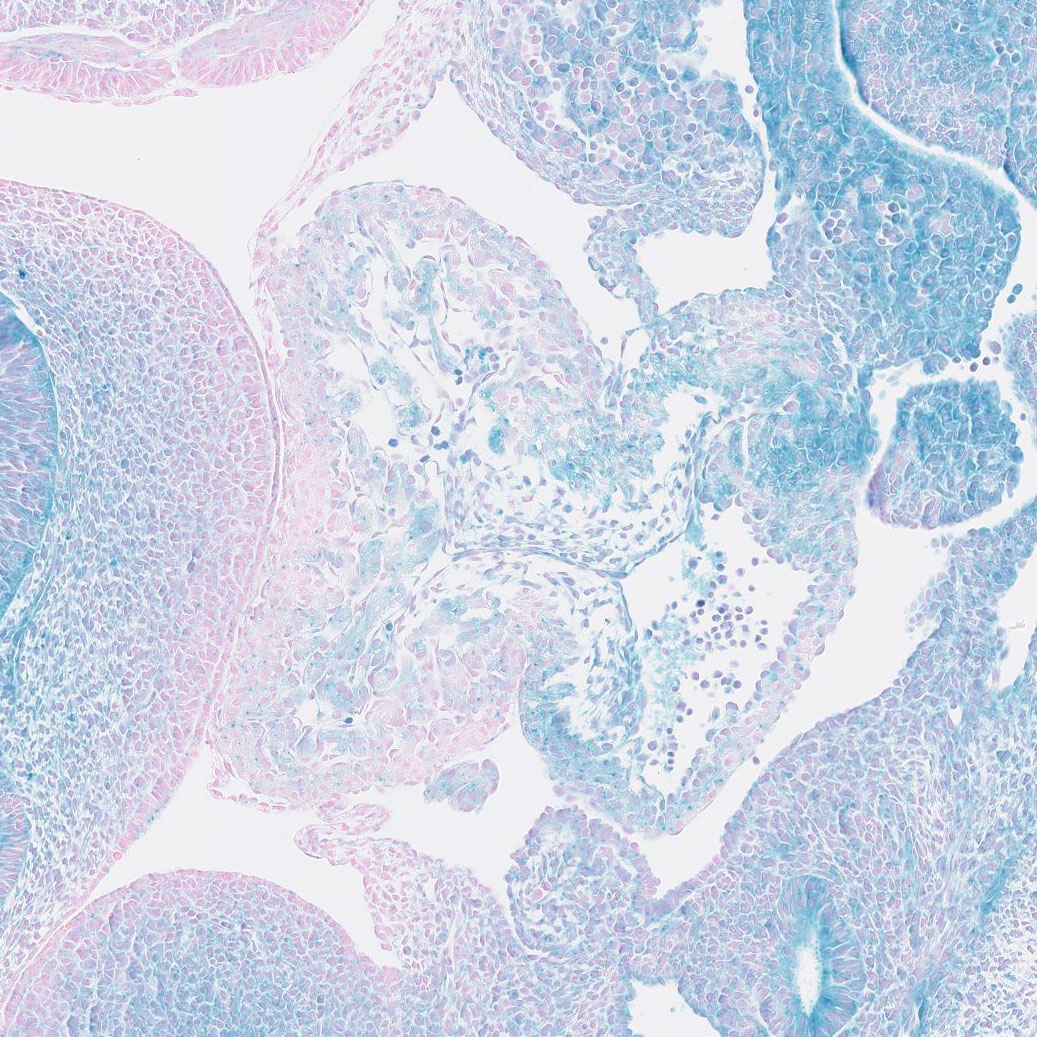

Fig. Wt1 P56 Muscle

J:216865

J:220957

Fig. S10